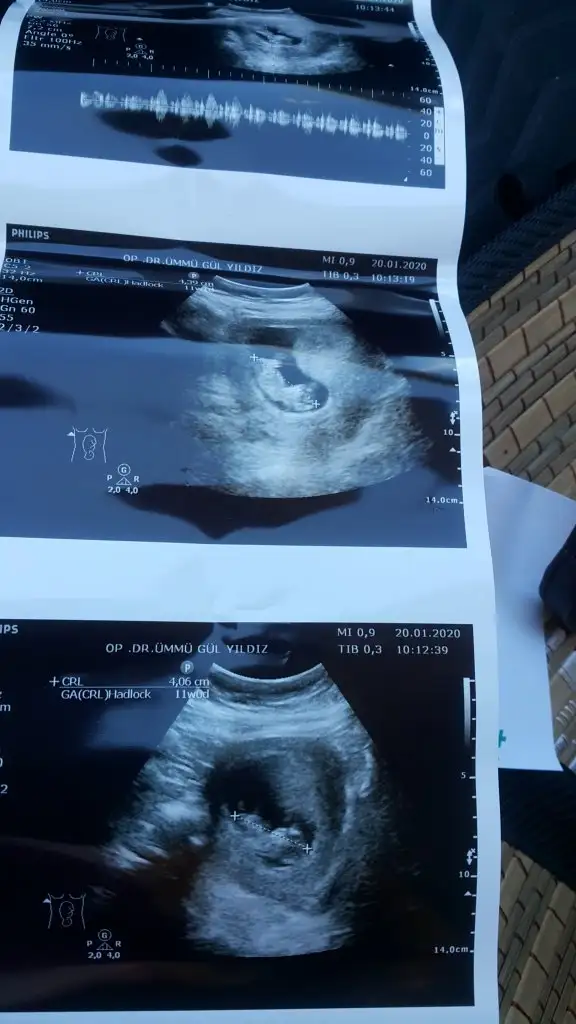

Tutmadı kız gibi dediniz ama doktor yanilmiyosa erkek dediSlm arkadaşlar nub teorisi konumuzda yaptıgım tahminleri ankete tıklayın yuzdesini görelim

Saglıkla gelsin usglerde nuba göre tahmin ediyorum bazen pozisyon çok degiştiriyor kaç haftalıkta erkek dedi yanılmıyorsa yazmışınızTutmadı kız gibi dediniz ama doktor yanilmiyosa erkek dedi

Ögrendinizmibu usg 12 +3 haftalık doktor %90 erkek dedi bu perşembe netleşecek